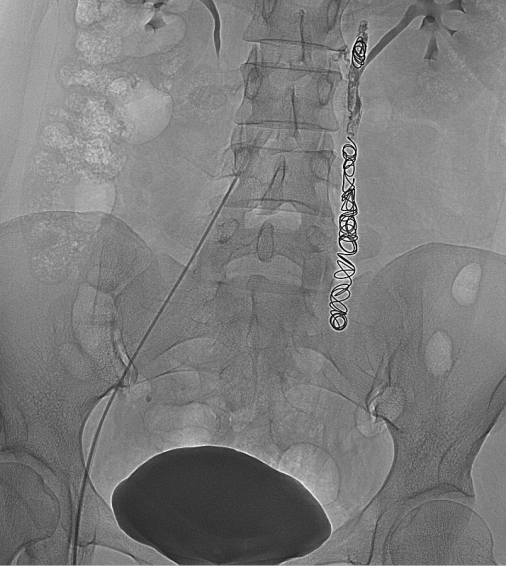

盆腔淤血综合征的介入治疗是在局部麻醉状态下,通过股静脉穿刺或颈静脉,引入导丝、导管,插入到盆腔静脉,进行盆腔静脉造影及予以硬化剂、金属弹簧圈等予以栓塞,将有病变扩张的盆腔静脉进行封闭,从而达到治疗的目的。

盆腔淤血综合征的介入治疗具有安全性高、创伤小、效果确切、不影响月经及生育的特点。